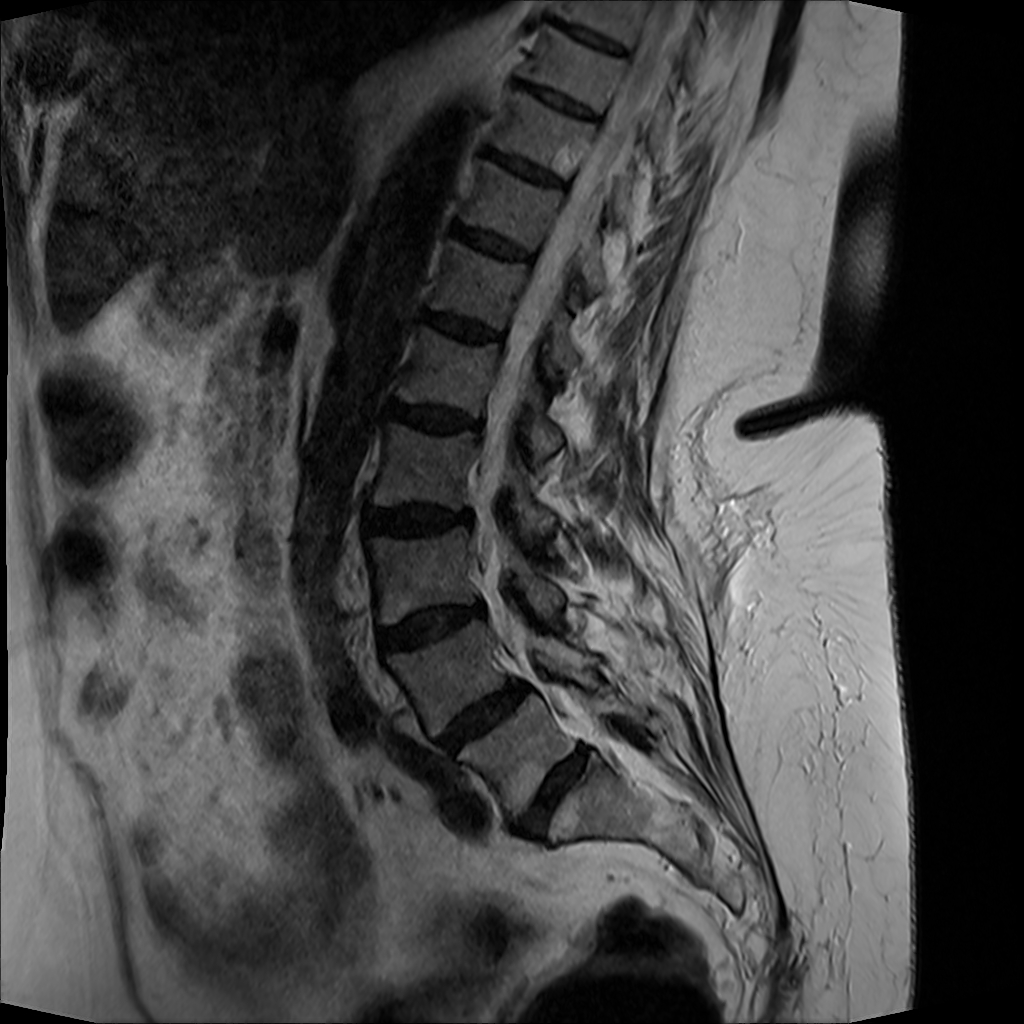

MRT Lendenwirbelsäule + Röntgen Becken - Diagnostik vor OP-Planung

19.01.2024

MRT Lendenwirbelsäule (LWS)

71 Bilder | 1024x1024 px | 15 MB

Januar 2024

MRT LWS + Röntgen Becken

MRT der Lendenwirbelsäule und Röntgen des Beckens zur Diagnostik

MRT LWS (Lendenwirbelsäule)

DICOM

MRT mit 71 Bildern